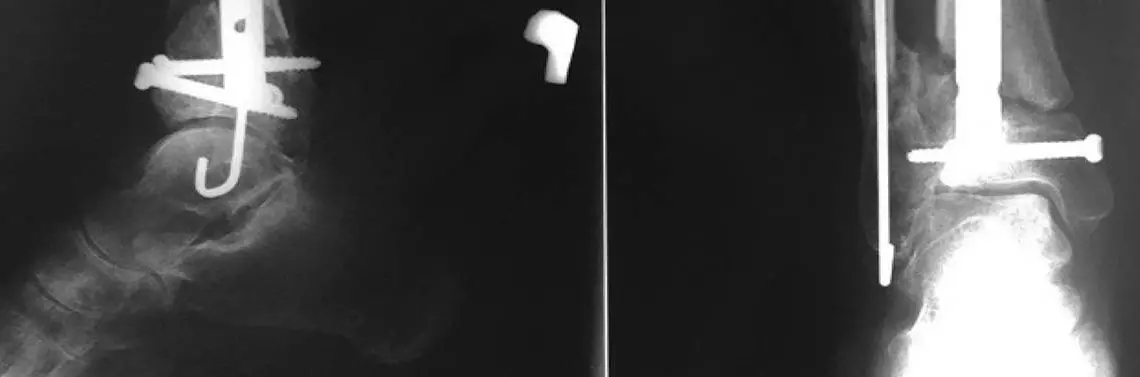

Diagnoza lekarza dyżurnego: złamanie otwarte II stopnia według Gustillo-Andersona, typ złamania według AO 43A3. Pacjentka została zakwalifikowana do etapowego leczenia operacyjnego. W trybie ostrego dyżuru wykonano operację polegającą na mechanicznym oczyszczeniu rany urazowej oraz odłamów kostnych (debridement) i ustabilizowaniu złamania przy użyciu dwupłaszczyznowego stabilizatora zewnętrznego. W okresie pooperacyjnym stwierdzono przedłużone gojenie się rany urazowej, wyciek treści patologicznej i narastające białko ostrej fazy (C-reactive protein – CRP). Wykonano kolejno dwie operacje w odstępie czterech dni, których celem było ponowne oczyszczenie. Za każdym razem śródoperacyjnie pobierano materiał do analizy mikrobiologicznej. Po normalizacji CRP i zagojeniu rany urazowej, tj. w 17. dobie od urazu, wykonano zamkniętą repozycję i przy użyciu śruby kaniulowanej zespolono fragment stawowy złamania, a następnie złamanie kości piszczelowej ustabilizowano przy użyciu gwoździa śródszpikowego rekonstrukcyjnego oraz kości strzałkowej drutem śródszpikowym typu TEN. Pacjentka została zaopatrzona w ortezę unieruchamiającą podudzie i staw skokowy. Dalszy przebieg gojenia rany był prawidłowy. Przez okres sześciu tygodni chora miała zakaz obciążania operowanej kończyny. Z powodu zrostu powolnego po trzech miesiącach wykonano kolejną operację: odświeżono szczelinę złamania pod kontrolą monitora RTG, podano przezskórnie PRP (ryc. 1). W szóstym miesiącu od operacji pierwotnej zdecydowano o dynamizacji zespolenia z powodu nadal niezadowalającego postępu zrostu w obrazie RTG, bez cech pourazowego zapalenia kości i przy prawidłowym obrazie klinicznym kończyny (ryc. 2). W kolejnych radiogramach wykonywanych co 6 tygodni obserwowano postępujący zrost kostny z brakiem przebudowy szczeliny złamania. W 12 miesięcy od operacji włączono leczenie aparatem Exogen (ryc. 3). W kolejnym RTG nie było dokonanej przebudowy szczeliny złamania, jednak z uwagi na kliniczne objawy zrostu i bezbolesny chód uznano złamanie za gojące się prawidłowo (ryc. 4). Pacjentce zezwolono na pełne obciążanie operowanej kończyny. Po 18 miesiącach od operacji stwierdzono zrost kostny odłamów, a w 36 miesięcy od złamania usunięto materiał zespalający (ryc. 5).